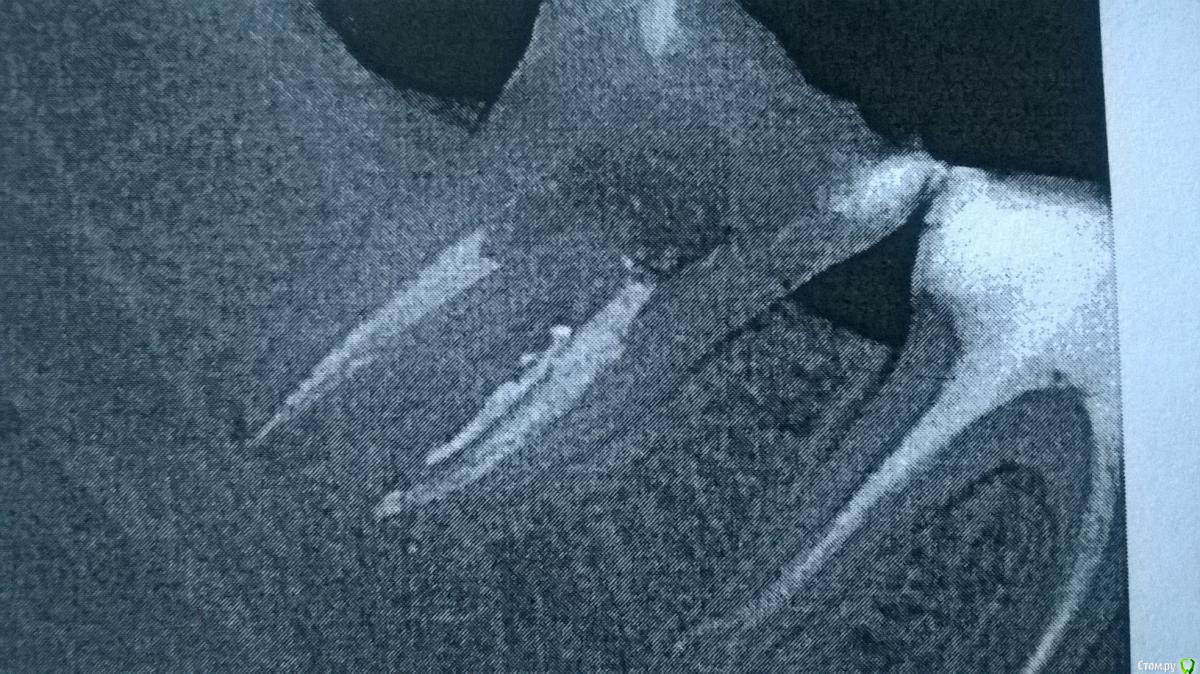

Lana54rus Опубликовано 23 мая, 2015 Поделиться Опубликовано 23 мая, 2015 (изменено) Доброго времени суток! очень нужен совет. Ситуация запутанная, но пытаюсь в ней хоть как-то разобраться.1) Итак: проходила стоматологическое лечение. Во время лечения начал ныть зуб 4.7. - ныл месяц (недепульпированный, живой), болел периодически. Доктору сообщала, но на это никто не отреагировал, ЭОД, и холодовую пробу не проводили, сказали, что на томограмме с этим зубом всё нормально. Спустя две недели попала по острой боли к другому доктору и на ранее выполненной дентальной томограмме заявили о наличии острого периодонтита (воспаление на верхушке корня) и записали на неотложку к другому доктору. Доктор промыл каналы, но прошёл их лишь наполовину (лечили под микроскопом), о чём мне и сообщил, (сказал, что так надо, полностью пройдут потом). Положил каласепт и закрыл всё временной пломбой, сказал придти через полторы недели. Когда чистили каналы, было зверски больно, не помогла даже анестезия.2) Через два дня стало совсем плохо - обратилась на неотложку в другую клинику (припухла щека и сильно ломила челюсть в области больного зуба). Пытались пройти каналы - доктор сказал, что один из каналов перфорированный, пытался пройти канал с перфорацией, но не получилось (при каждом посещении ставил пасту "каласепт")..3) Обратилась в другую клинику, где также попытались пройти каналы, но потом сообщили, что там ложный канал и сказали о срочной необходимости данный зуб удалить.4) Я отказалась, пошла к другому доктору. Доктор сказал, что зубы с перфорациями лечат, а не удаляют - все каналы прошли, перфорацию закрыли. Запломбировали каналы сразу же на постоянной основе. Зуб болел ещё две недели после пломбировки каналов, успокоился только неделю назад. Вчера поставили постоянную пломбу. К своему последнему доктору, претензий нет никаких, доктор что мог, то сделал.Вопрос (для собственного успокоения и чтобы хоть как-то понять ситуацию):1. Каковы прогнозы для подобного зуба?2. Учитывая вышеизложенное, а также картину на снимках о чем здесь следует говорить: об остром или хроническом периодонтите (ранее была высказана гипотеза, о том, что у меня уже был периодонтит и нерв в зубе умер уже давным давно). На данный момент томографией из первой клиники не располагаю, а потому могу обрисовать ситуацию лишь на словах.Заранее, спасибо за ответы.а) снимок сделанный во время лечения во второй клинике;б) снимок во время прохождения каналы сделанный в третьей клинике, где зуб настоятельно рекомендовали удалить;в) окончательный вариант пломбировки каналов. Изменено 23 мая, 2015 пользователем Lana54rus Ссылка на комментарий